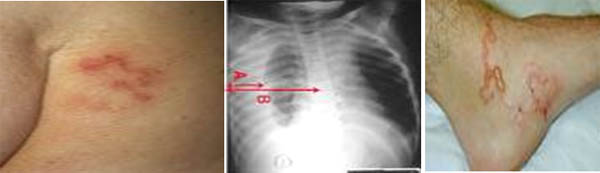

Bệnh giun lươn mãn tính, không biến chứng có thể gặp ở người bình thường, không có suy giảm miễn dịch, đa số không có triệu chứng. Nếu có thường biểu hiện ở da như những đường ngoằn ngoèo ở da, bầm máu, nổi mề đay. Biểu hiện ở đường tiêu hoá như đau bụng, tiêu chảy, ngứa hậu môn, sụt cân nhẹ,....Trường hợp nặng, có biến chứng gặp ở người suy giảm miễn dịch. Người bệnh có thể gặp các biến chứng như tắc ruột, viêm phổi, viêm não, nhiễm trùng huyết. Tuỳ theo vị trí ký sinh của ấu trùng trong cơ thể, bệnh nhân có những biểu hiện khá nhau. Do vậy, việc chẩn đoán phải dựa vào huyết thanh miễn dịch học.

- Ở da: Có những đường ngoằn nghèo (thường là ngang thắt lưng, quanh hậu môn) do ấu trùng di chuyển. Các vết bầm máu (kích thước khoảng 3-4 cm) rải rác ở các chi, thân mình và nổi mề đay.

Ngoài ra, bệnh nhân có thể ho, viêm phổi (X- quang phổi có vùng thâm nhiễm), viêm đa khớp, đau cơ. Có trường hợp tìm thấy ấu trùng giai đoạn 1 trong nước tiểu.

- Đường ngoằn nghèo ở da, thường ngang thắt lưng & quanh hậu môn

- Da: gây hội chứng ấu trùng di chuyển ngoài da tạo ra những đường đỏ, chạy ngoằn ngoèo dưới da, ban xuất huyết, chấm xuất huyết dưới da.

- Nhiễm trùng da niêm mạc: sự xuyên thấu qua da của ấu trùng (filariform larvae) giun lươn đầu tiên thường gây ra triệu chứng nhẹ hoặc không có triệu chứng. Các đợt nhiễm trùng tiếp theo hoặc lặp lại có thể gây ra phản ứng dị ứng với dị nguyên là ấu trùng xuyên da, nhất là những người có phản ứng quá mẩn thì ấu trùng chỉ có thể dừng lại ở giai đoạn này mà không đến được giai đoạn phổi. trong quá trình di chuyển trong da, chúng có thể gây nên hội chứng nhiễm lan tỏa (creeping eruption) hay hội chứng ấu trùng di chuyển (larvae migrans).

- Nhiễm trùng tại phổi: ở phổi, ấu trùng di chuyển và gây phản ứng do quá trình ấu trùng giun lươn nhiều trong mao mạch phổi, vào trong phế nang, tạo ra các chấm xuất huyết nhỏ và thâm nhiễm tế bào tại phế quản và phế nang. Viêm phổi xảy ra ở những bệnh nhân có cơ địa mẩn cảm rất mạnh với các sản phẩm tiết từ ấu trùng giun lươn nói riêng và các ký sinh trùng nói chung, điều này khiến làm chậm sự di chuyển chúng qua phổi và một trong số chúng bị chết do phản ứng này. Trong pha nhiễm này thì ấu trùng có thể tìm thấy trong đờm bệnh nhân. Trong một vài trường hợp, viêm phế quản mạn tính hoặc hội chứng hen với trứng và ấu trùng thể rhabditiform có thể thấy được.